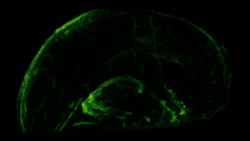

Although several studies proposed the existence of lymphatic vessels in the dura mater, the presence of the meningeal lymphatic system was accepted in 2015, when two independent studies published by Louveau et al.[1] and Aspelund et al.[2] provided convincing data using novel methods. Louveau et al. noticed an unusual alignment of immune cells along the dural sinus using a meningeal whole-mount technique. Using lymphatic endothelial cell-specific markers and electron microscopy, the authors found that the immune cells were not inside blood vessels, but rather were organized inside lymphatic vessels within the meninges, a system of membranes that envelop the brain and spinal cord.[1]

In transgenic mice containing Prox1-GFP or Vegfr3-LacZ reporter genes, the lymphatic vessels may be visualized by fluorescent microscopy or after X-gal staining, respectively.[2]